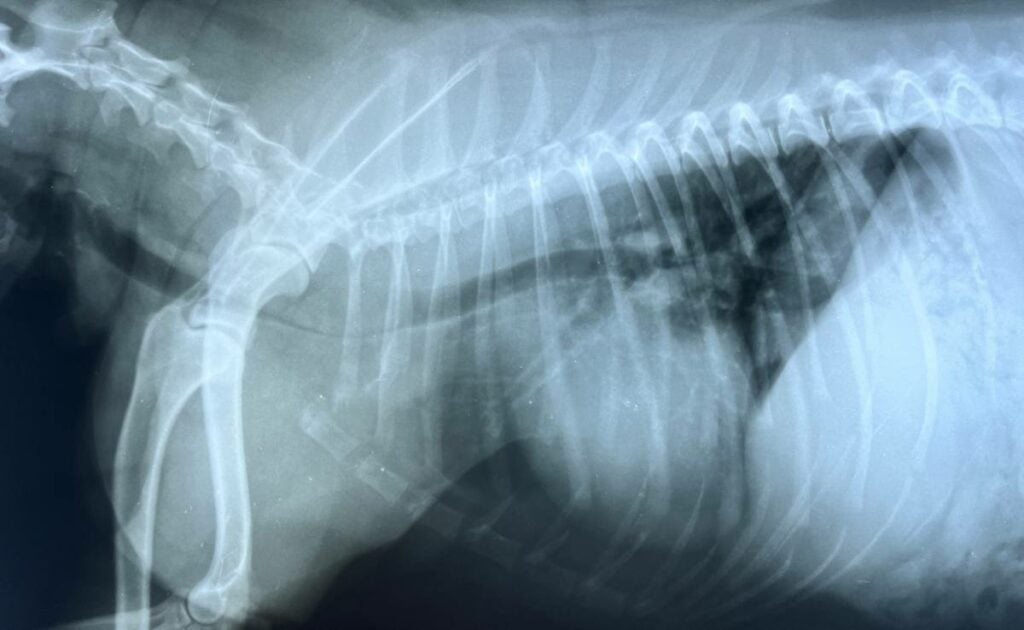

Your veterinarian may perform a complete physical exam, nasal swab testing, temperature check, chest X-rays (if pneumonia is suspected), and blood work (in severe cases).

Most cases do not require hospitalization, but vets may recommend oxygen therapy for dogs with breathing challenges.